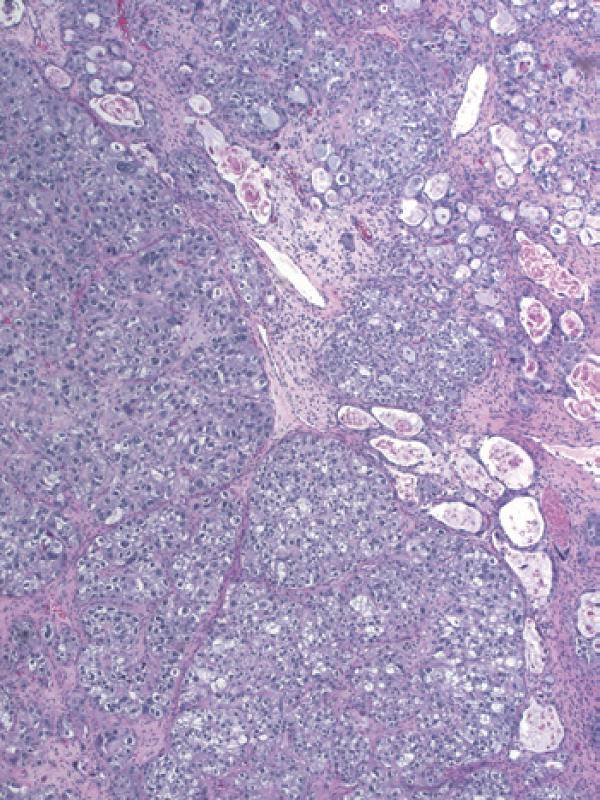

彩图4-2 卵巢透明细胞癌呈现典型管状囊性结构

彩图4-3 卵巢透明细胞癌

乳头状结构中基质玻璃样变是许多透明细胞癌乳头中的典型特征

彩图4-4 典型混合细胞类型卵巢透明细胞癌,少量管状囊性结构(右上)与大量含透明细胞质的细胞结节样生长共存(左下)